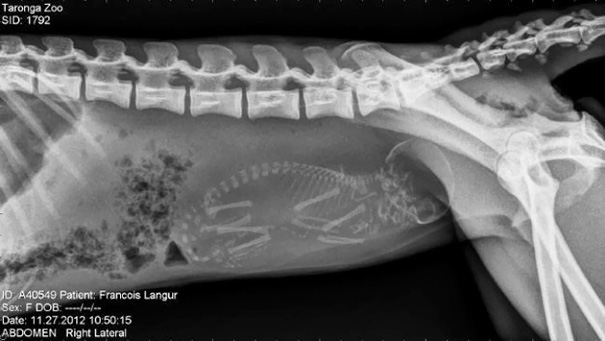

Load More Replies...An X-Ray Of A Pregnant Francois Langur Monkey